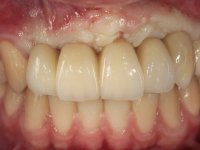

O paciente foi observado conjuntamente e a dúvida que surgiu de imediato foi se seria possível com a regeneração óssea a efectuar poder ser reabilitada naturalmente a zona das papilas interdentárias. Nesse sentido foi feito um enceramento de diagnóstico que contemplaria as duas hipóteses, utilizando ou não a cerâmica gengival. A confecção desse enceramento foi fundamental para expor ao paciente a dificuldade da reabilitação. O wax-up deu origem a um mock-up que foi aprovado pelo paciente e que simultaneamente serviu de guia imagiológica. O caso foi planificado cirurgicamente e realizada uma guia cirúrgica com que foram colocados os implantes. Após 10 semanas foi feita a 1ª impressão para confecção da ponte provisória. Foram criados os primeiros perfis de emergência na gengiva artificial e foi digitalizado o modelo. Por processo de CAD-CAM foi confeccionada uma ponte provisória aparafusada baseada no enceramento de diagnóstico. A ponte trabalhou durante 8 semanas os tecidos moles que foram fielmente copiados numa impressão com técnica de moldeira aberta. Os transferes foram individualizados com resina composta para copiarem fielmente os perfis de emergência criados pela ponte provisória. Confeccionado o modelo de trabalho definitivo, foi realizada uma infra-estrutura em zircónio seguindo a orientação do enceramento de diagnóstico. O assentamento da infra-estrutura foi testado em boca e simultaneamente foi novamente impressionados os tecidos moles com um silicone fluido. Nessa consulta foi feito o levantamento da cor. Os dentes 13 e 23 apresentavam uma saturação anormalmente forte que resolvemos não valorizar, optando por privilegiar a relação com o sector antero-inferior. Foi realizada uma nova gengiva artificial com a impressão que acompanhou a impressão de arrasto com a infra-estrutura. Após a colocação da cerâmica na infra-estrutura foram coladas as meso-estruturas. O trabalho final foi aparafusado lentamente permitindo a adaptação dos tecidos moles.